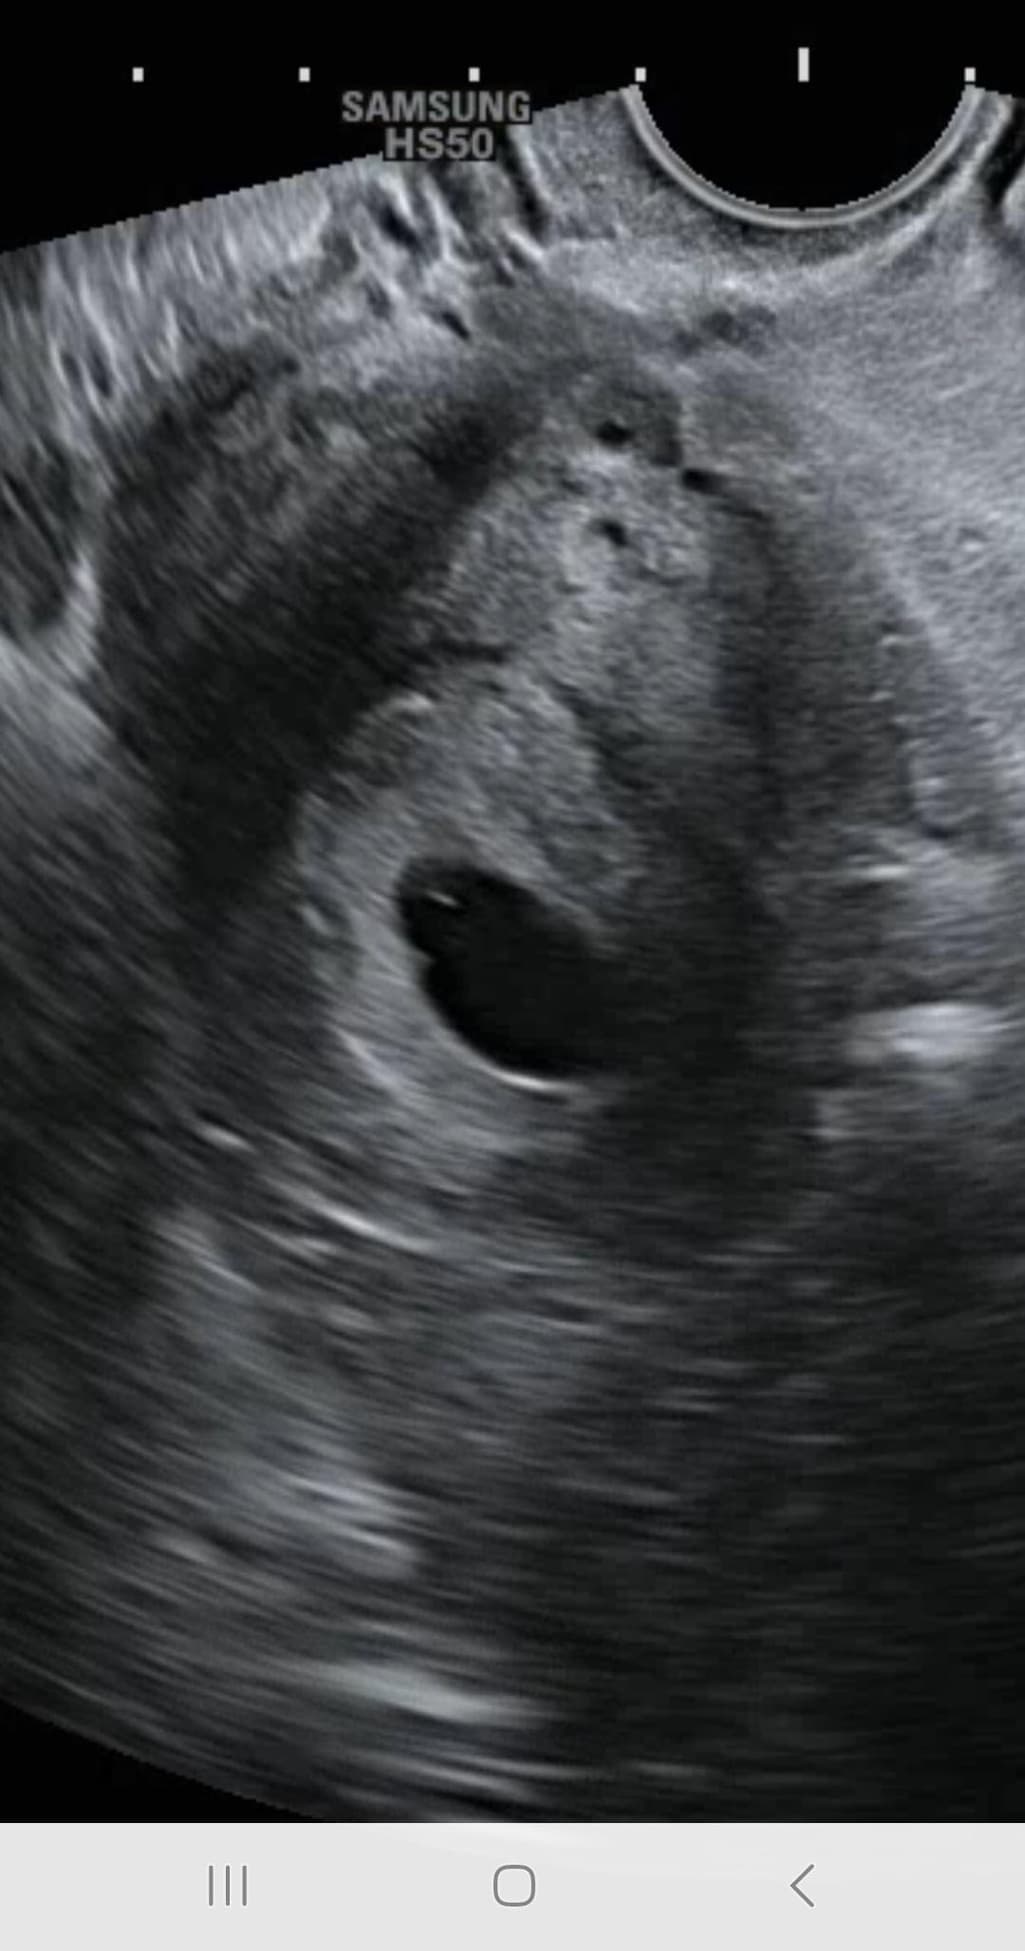

제가 생리가 불규칙 한데 마지막 생리가 3월3일이구요 임신 확인했고 아기집을 보고 왔는데 오늘 병원가서 검사하는데 8주인데 아기가 안보이고 심장뛰는게 안보인다고 하셨어요..ㅠ 제가 그동안 출혈 자체도 없었는데 진짜.. 유산인가요??ㅠ 난황도 없나요?ㅠ